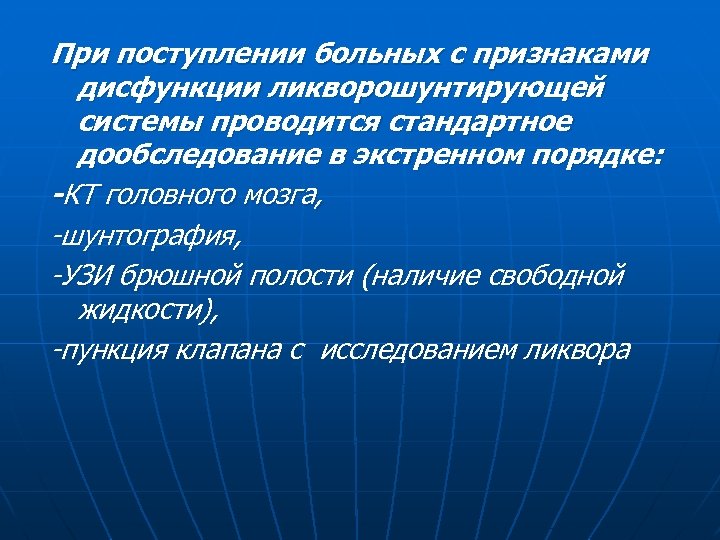

При поступлении больных с признаками дисфункции ликворошунтирующей системы проводится стандартное дообследование в экстренном порядке: -КТ головного мозга, -шунтография, -УЗИ брюшной полости (наличие свободной жидкости), -пункция клапана с исследованием ликвора

ВЫВОДЫ: n n n Детям после ЛШО в дальнейшем почти всегда требуются повторные вмешательства Необходимо избегать необоснованных ЛШО При выполнении ликворошунтирующих операций важно соблюдение всех правил имплантации При поступлении больного с осложнениями после ЛШО показано выполнение диагностических мероприятий (КТ головного мозга, УЗИ ОБП, пункция помпы клапана, исследование ликвора) в экстренном порядке ! Использование видеоэндоскопии при ревизиях ВПС